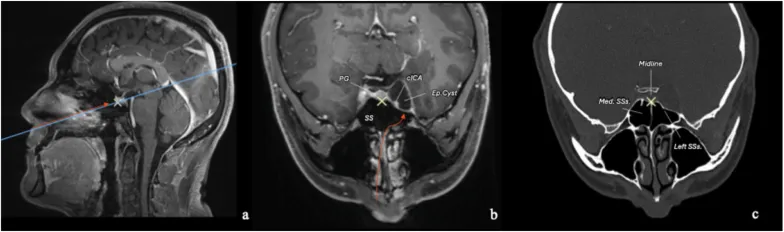

图3:对侧单鼻孔内镜经鼻入路的术前影像规划。规划使用Carestream Image Suite软件进行,图像在空间上同步。图中蓝色线条指示图像的方位。黄色十字在所有三幅图像中共同配准,用于识别垂体。橙色箭头指示计划的手术路径。囊肿在海绵窦外侧隔腔内、颈内动脉海绵窦段与海绵窦外侧壁之间形成了一个自然的的手术通道。骨窗CT扫描对于理解蝶窦解剖至关重要。在本例中,蝶窦中隔标识了蝶鞍和中线,而较小的左侧间隔附着于左侧颈内动脉隆起。基于此解剖结构,可采用对侧经鼻甲前部入路抵达左侧海绵窦,无需完全蝶窦切开,从而保留了右侧蝶窦。

图5:术前及术后轴位、冠状位骨窗CT扫描,展示采用右侧对侧单鼻孔内镜经鼻入路处理左侧海绵窦病变。术前扫描显示蝶窦中隔位于中线,左侧蝶窦间隔附着于左侧颈内动脉海绵窦段隆起。这些间隔是重要的蝶窦内解剖标志。术后扫描显示,通过左侧经鼻甲前部通道,仅进行了左侧半蝶窦切开。鞍旁迷你骨窗已重建,左侧半蝶窦用腹部脂肪填塞,鼻甲前部粘膜已缝合。鼻腔解剖结构得到了最大程度的保留。缩写:Med. SSs.:蝶窦中隔;SSs.:蝶窦间隔。